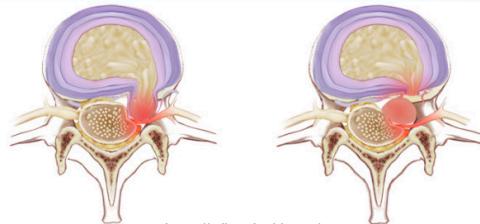

Pathological Progression

- Bulge → Back pain

- Protrusion → Sciatica

- Prolapse & Sequestration → Neurological deficits

Disc is formed of:

- Nucleus pulposus

- Annulus fibrosus

Pathology

- Prolapse & sequestration → numbness, paresthesia, weakness